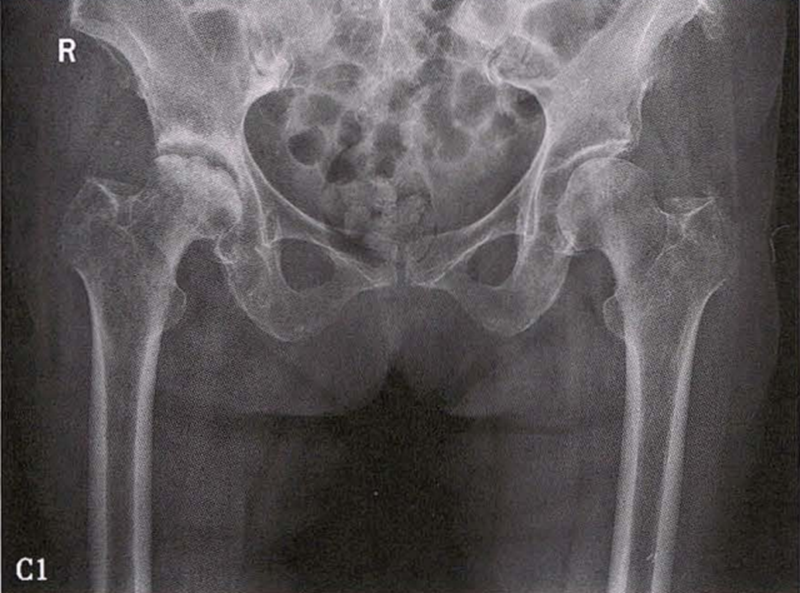

(1)X线检查 X线是诊断股骨头坏死的首选检查手段,常规拍摄髋关节正侧位片。早期股骨头坏死X线片可正常或显示股骨头外上方骨小梁稀疏;病情进展后逐渐出现密度增高、硬化带、囊性变等;晚期则出现股骨头塌陷、关节间隙变窄、Shenton's线不连续、骨关节炎改变等。硬化带和新月征是股骨头坏死X线特征性表现。在股骨头关节面塌陷变形早期上关节间隙不变或增宽后期随着骨关节炎加重关节间隙逐渐狭窄。

X线检查示右侧股骨头骨质密度不均匀

C.女性,89岁,右侧股骨头坏死Ⅳ期。X线片示右侧股骨头压缩变扁,右侧髂臼密度增高,关节内侧间隙狭窄、不均匀(C1)。MRI示右股骨头压缩变扁,右髋关节腔比较多积液(C2)。